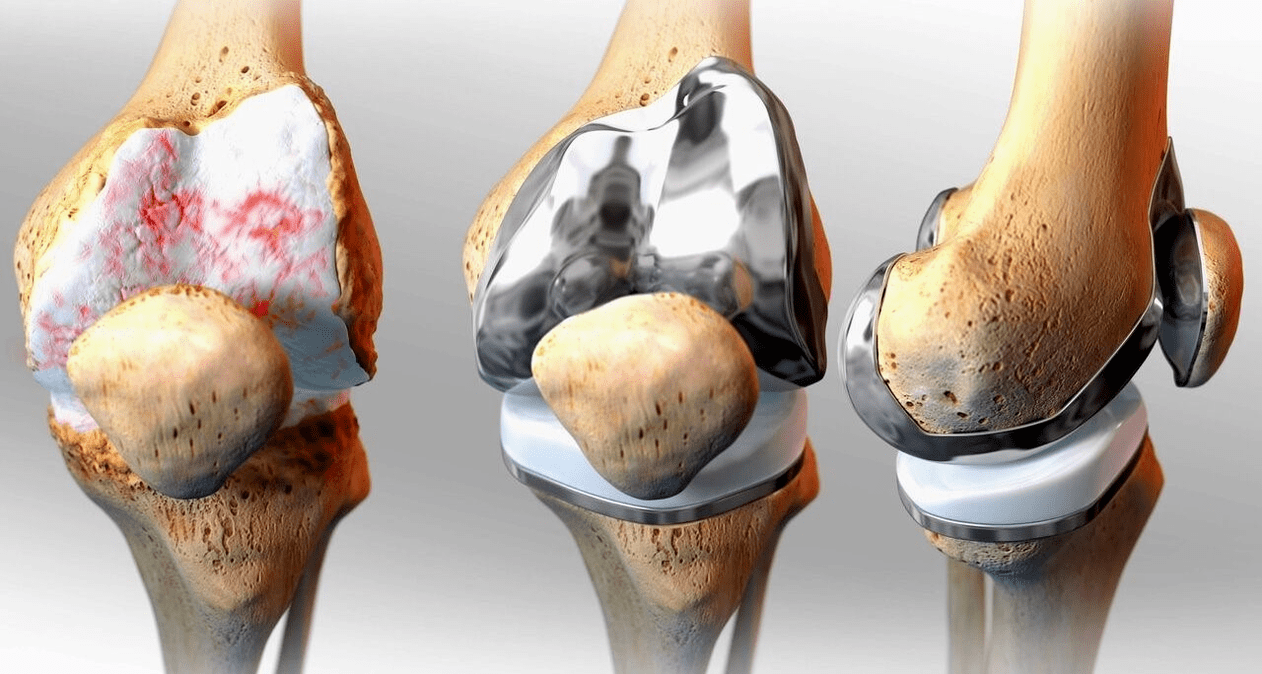

Chirurginis — artroskopija (mažai trauminis intraartikulinių patologijų gydymo ir pažeistų struktūrų šalinimo metodas), endoprotezavimas.

Chirurginis gydymas ir endoprotezavimas

Endoprotezo keitimas yra įprastas ir veiksmingas chirurginis sunkios gonartrozės gydymo metodas, leidžiantis išlaikyti galūnių mobilumą ir galimybę vėliau gyventi visavertį gyvenimą. Tai aukštųjų technologijų operacija, trunkanti maždaug pusantros valandos. Pooperaciniu laikotarpiu būtina ilgalaikė reabilitacija ir sąnario vystymas. Po 25-30 metų, kai susidėvi dirbtinis sąnarys, jį vėl reikia keisti.